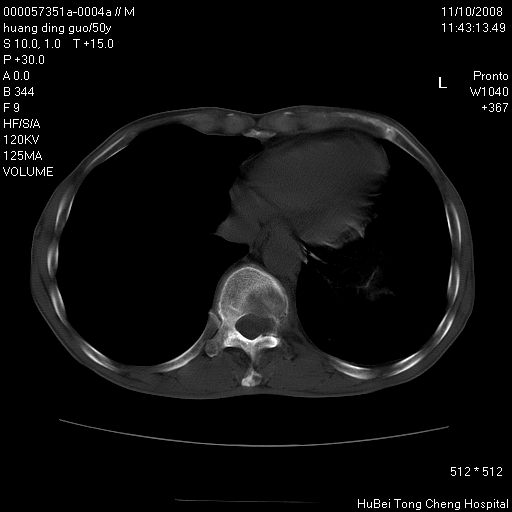

患者 男,50岁。左侧腰背部疼痛3月余,伴消瘦。平素健康,无传染病史。

胸部ct轴位平扫(层厚10mm,螺距1.5,重建间隔10mm),图像如下:

左肺下叶背段有一厚壁空洞,外壁呈锯齿状伴毛刺改变。空洞相邻胸膜有牵拉改变。左肺下叶血管支气管束不规则增粗,小叶间隔增厚。胸椎骨质破坏。考虑左肺下叶周围型肺癌伴左肺下叶癌性淋巴管炎、胸椎转移。

支持:左肺周围型肺癌伴癌性淋巴管炎\\胸椎转移瘤,不除外肺泡癌。(椎体破坏伴椎弓破坏)

左肺下叶背段有一厚壁空洞,外壁呈锯齿状伴毛刺改变。空洞相邻胸膜有牵拉改变。左肺下叶血管支气管束不规则增粗,小叶间隔增厚。胸椎骨质破坏。考虑左肺下叶周围型肺癌伴阻塞性肺炎、胸椎转移。其他待排

左肺下叶背段有一厚壁空洞,外壁呈锯齿状伴毛刺改变。空洞相邻胸膜有牵拉改变。左肺下叶血管支气管束不规则增粗,小叶间隔增厚。胸椎骨质破坏。考虑左肺下叶周围型肺癌伴胸椎转移。

左肺下叶背段有一厚壁空洞,内壁不规则,外壁呈锯齿状伴毛刺改变。空洞相邻胸膜有牵拉改变。周围呈絮状炎性改变,左肺下叶血管支气管束不规则增粗,小叶间隔增厚。胸椎骨质破坏。考虑左肺下叶周围型肺癌伴左肺下叶阻塞性肺炎、胸椎转移。